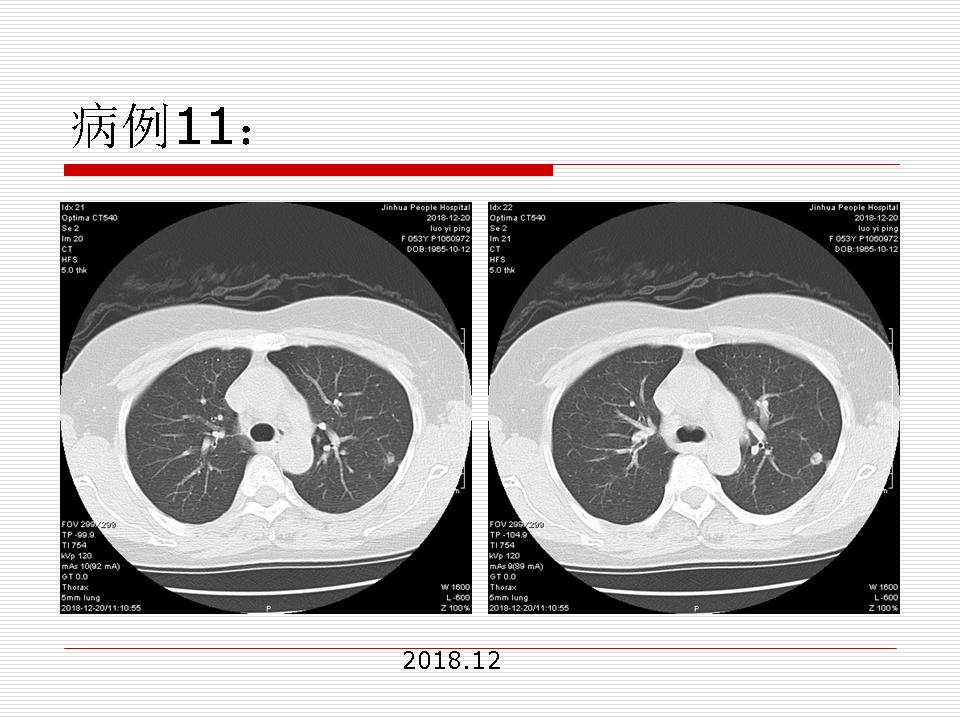

肺部阴影永恒且最重需要鉴别的是:到底是炎症还是肿瘤?但临床的病例中的影像表现难以界定或有些肿瘤特征,同时又有些炎症特点是非常常见的情况。作为临床医生我们怎么去总结分析,并找到之所以是炎症或之所以是肿瘤的细微差别或特点非常重要,也非常有用。2019.12.7浙江省2019年胸心外科学学术年会在宁波召开时,我的临床病例分析与经验总结<那些像肺癌的炎症与像炎症的肺癌>获得在大会交流的机会,以下为该PPT的内容,与你分享,希望对同道有益,有借鉴与启迪。若有探讨与进一不完善的建议,欢迎文末留言讨论: